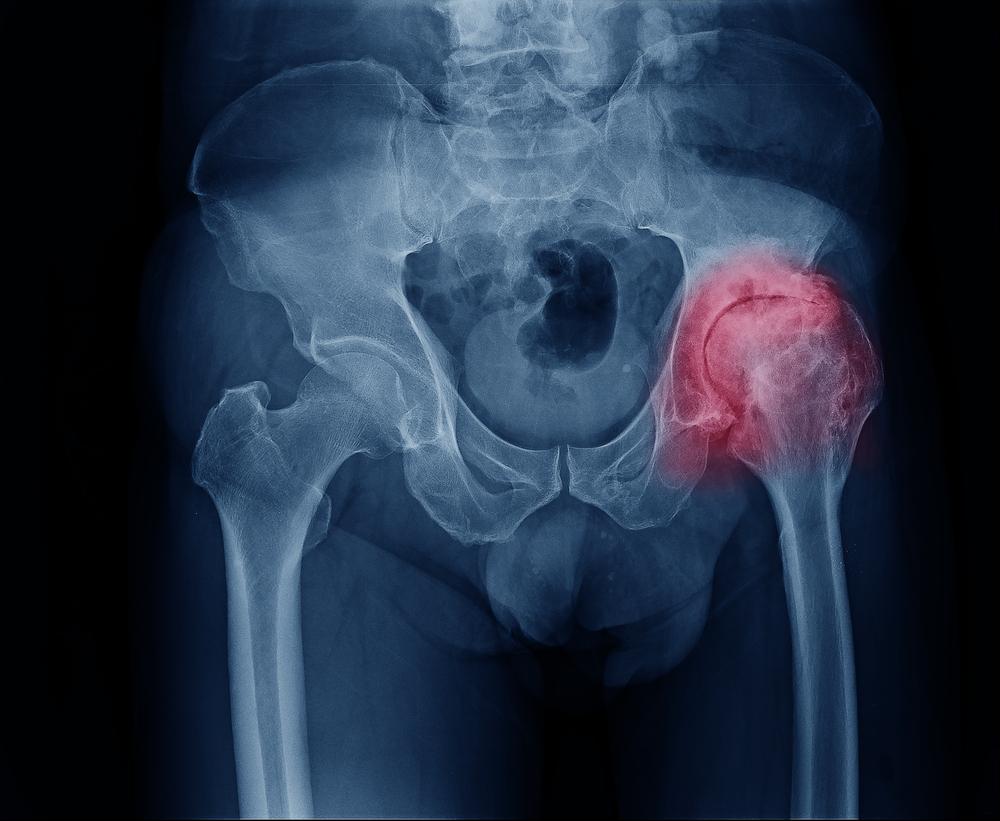

Тазобедренный сустав – самый крупный в человеческом теле. Он испытывает колоссальные нагрузки и часто подвергается различным заболеваниям. Артрит – это болезнь, которая поражает как взрослых, так и детей разного возраста. Воспаление часто развивается вследствие травм, инфекционного процесса или сбоев в работе иммунитета. При отсутствии терапии последствия недуга могут быть очень тяжелыми, вплоть до инвалидности и смерти ребенка.

Артрит тазобедренного сустава у детей может иметь различные причины, включая инфекционные, аутоиммунные и травматические факторы. Врачи отмечают, что наиболее распространенными формами являются ювенильный идиопатический артрит и реактивный артрит, возникающий после инфекций. Симптомы могут варьироваться от болей в суставе и ограниченной подвижности до отека и покраснения. Для диагностики специалисты используют клинический осмотр, анализы крови и визуализационные методы, такие как УЗИ и МРТ. Лечение зависит от причины и может включать противовоспалительные препараты, физиотерапию и в некоторых случаях хирургическое вмешательство. Важно, чтобы родители обращались к врачу при первых признаках заболевания, чтобы избежать осложнений и сохранить здоровье ребенка.